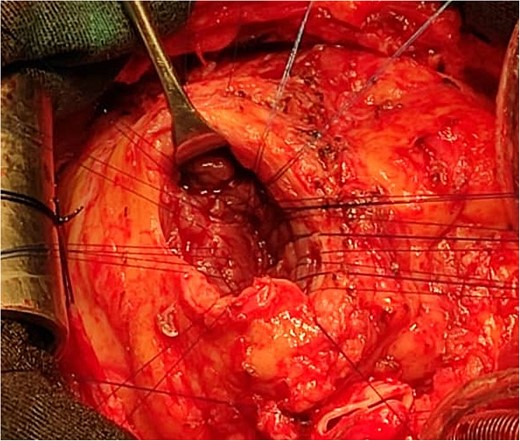

An 11-year-old girl was referred to our hospital with a main complaint of progressive exertional dyspnea. She had undergone surgical repair of SAS 6 years ago. Transthoracic echocardiogram (TTE) revealed the following findings: severe left ventricular hypertrophy, tunnel-like fibromembranous subaortic stenosis with a length of 10 mm, a peak gradient (PG) across the LVOT of 170 mmHg, and mild aortic regurgitation. Based on these findings, the patient was scheduled for elective surgical repair with a possible indication for MKO. The operation was performed via median sternotomy with great caution to avoid inadvertent rupture of any cardiac cavity due to heavy adhesions from the previous operation. The aorta was cannulated just below the takeoff of the innominate artery. Bicaval cannulation was performed to provide a bloodless field. Aortic cross-clamping was applied, and antegrade cold blood cardioplegic solution was administered via a catheter placed in the ascending aorta. The ascending aorta was opened transversely 1 cm above the sinotubular junction (Fig. 1). The aortic valve leaflets were examined carefully to confirm that the aortic valve could be preserved. LVOT was examined thoroughly, and it was clear that the stenosis in the subaortic area was so complex that simple resection through the aortic valve orifice would not be sufficient. The right ventricular outflow tract was opened transversely below the pulmonary valve. The conal papillary muscle was identified (Fig. 2). A right-angle instrument was introduced through the aortic orifice into the interventricular septum, and the tip of the instrument was used to perforate the conal septum to the left of the conal papillary muscle to prevent damage to the conduction system; the septal incision was completed with great caution to avoid damage to the aortic cusps and to extend the incision downward as necessary to completely relieve the stenotic subaortic area (Fig. 3). Interrupted 5/0 Prolene sutures were placed circumferentially around the septal incision to close the interventricular septal defect using a bovine pericardial patch to provide adequate widening of LVOT (Fig. 4). The right ventriculotomy was closed with a second bovine pericardial patch to avoid any possible obstruction of the right ventricular outflow tract (Fig. 5). The remainder of the operation was completed uneventfully. After 6 hours of mechanical ventilation, the patient was extubated, and she convalesced well postoperatively. TTE showed excellent results of the operation with PG across LVOT of 20 mmHg. On 1 year follow-up, the patient was asymptomatic and in very good general condition, and TTE findings confirmed the excellent result.

Intraoperative image showing the opened aorta. The arrow points to the aortotomy, and the star points to the stenotic left ventricular outflow tract through the aortic orifice.